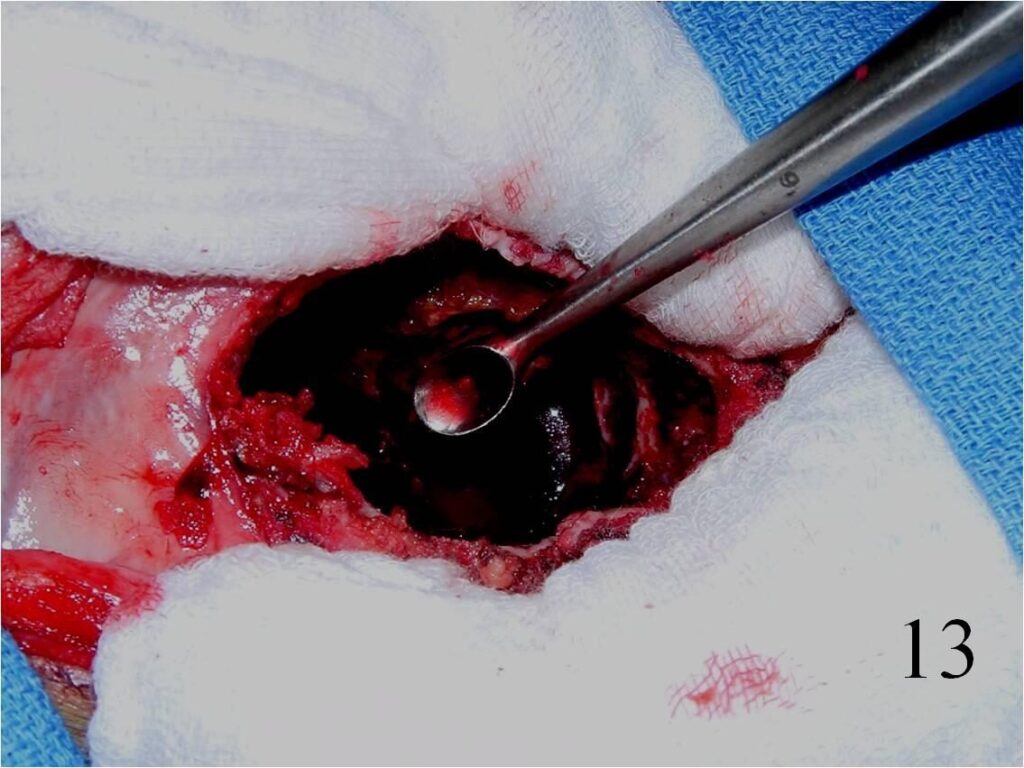

o Curettage, cement and possible internal fixation with hardware (Fig. 13, 14, 16)

Fig. 13 Intralesional curettage of the giant cell lesion and (Fig. 14) shaving the wall of the tumor cavity with high speed burr.